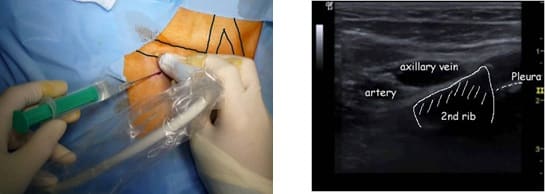

3. Acceso por la vena subclavia en adultos

La vía subclavia en comparación la vía yugular es más funcional y estética evitando muchas de las complicaciones relacionadas con la punción a ciegas.

Además, no es necesario tunelizar, es un abordaje más cómodo et rápido.

Hoy en día, nuestra vía de abordaje de elección era la vena subclavia en el surco deltopectoral, lo cual permite una gran discreción para los pacientes (respeto del escote). Colocamos el 99% de nuestros puertos con este abordaje.

Se punciona la vena en el fondo del bolsillo: de esta manera el catéter tiene un recorrido más fisiológico y evitamos los posibles curvas o acodamientos que pueden crearse cuando la vena se punciona desde otro lugar.

2. Fundamentos ecográficos a conocer para acceder a la vena

El acceso a la vena yugular se realiza bajo control ecográfico mediante abordaje lateral con una curva más fisiológica del catéter.

La sonda es ortogonal a la vena pero la aguja es paralela al eje principal de la sonda, como visto anteriormente.

Esto hace que sea mucho más fácil seguir la aguja en casi todo su recorrido: